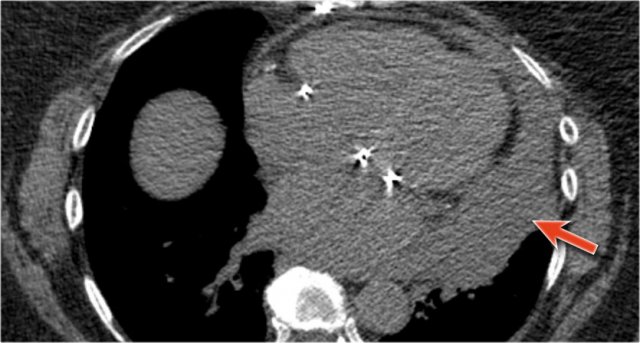

CT correlation

The explanation for the cardiac incisura is seen on this CT-image.

At the level of the inferior heart, the right lower lobe (blue arrow) is often seen extending more anteriorly than the left lower lobe (red arrow) , explaining the asymmetry of the cardiac incisura.